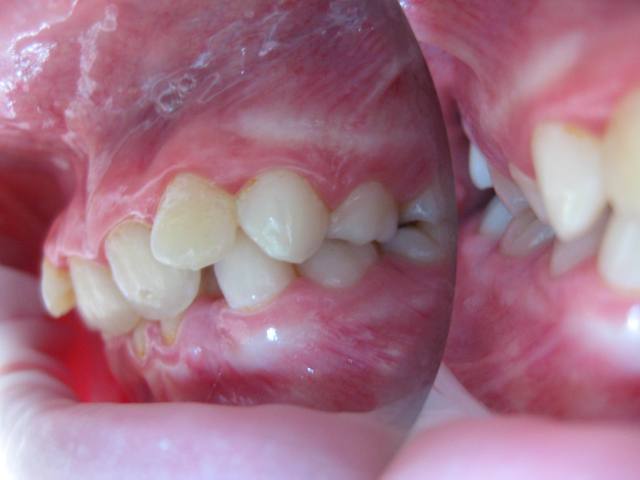

Photos endobuccales  1  ap7xrd - Eugenol

Elle présente une linguo-version et une égression des incisives maxillaires et mandibulaires. Le truc c'est que les racines de 11 et 21 semblent bien positonnées sur la télé de profil, alors que les faces vestibulaires sont très lingualées.

C'est une Cl II/2 non ?

Je ne sais pas si ta question est sérieuse? Tu fais l'analyse céphalo, les photos et tu te poses la question quoi faire? C'est une classeII 2.Si tu ne fais pas de l'ortho, adresse car c'est le bon moment pour traiter et dévérouiller. Quant à la dévitalisation j'espère que c'était de l'humour.

Jeamba, je me demandais que faire uniquement par rapport à l'angulation entre les axes radiculaire et coronaire des incisives. Pour le reste j'ai vu que c’était une classe II2